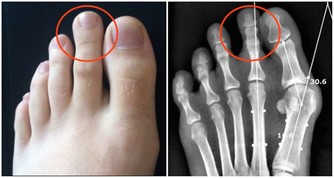

染髮劑中的PPD,還能導致過敏。

歐洲國家曾做過調查,普通人群接觸PPD過敏率為0.1%—1.0%,

在泰國高達2.3%,就是說100個用過染髮劑的人起碼2個人過敏。